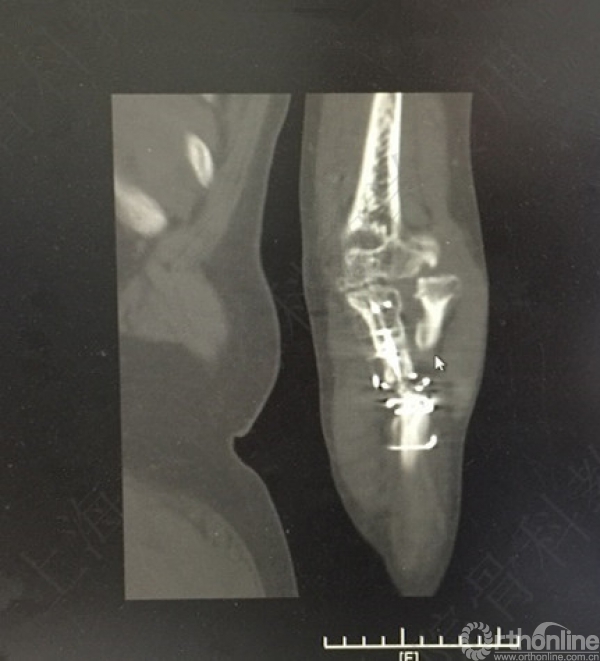

X线及CT示:左尺桡骨骨不连,尺骨力线差,成角,桡骨头脱位,创伤性关节炎。

患者择期行左尺桡骨取原内固定+切开复位内固定术+髂骨异体骨植骨+桡骨头切除术。